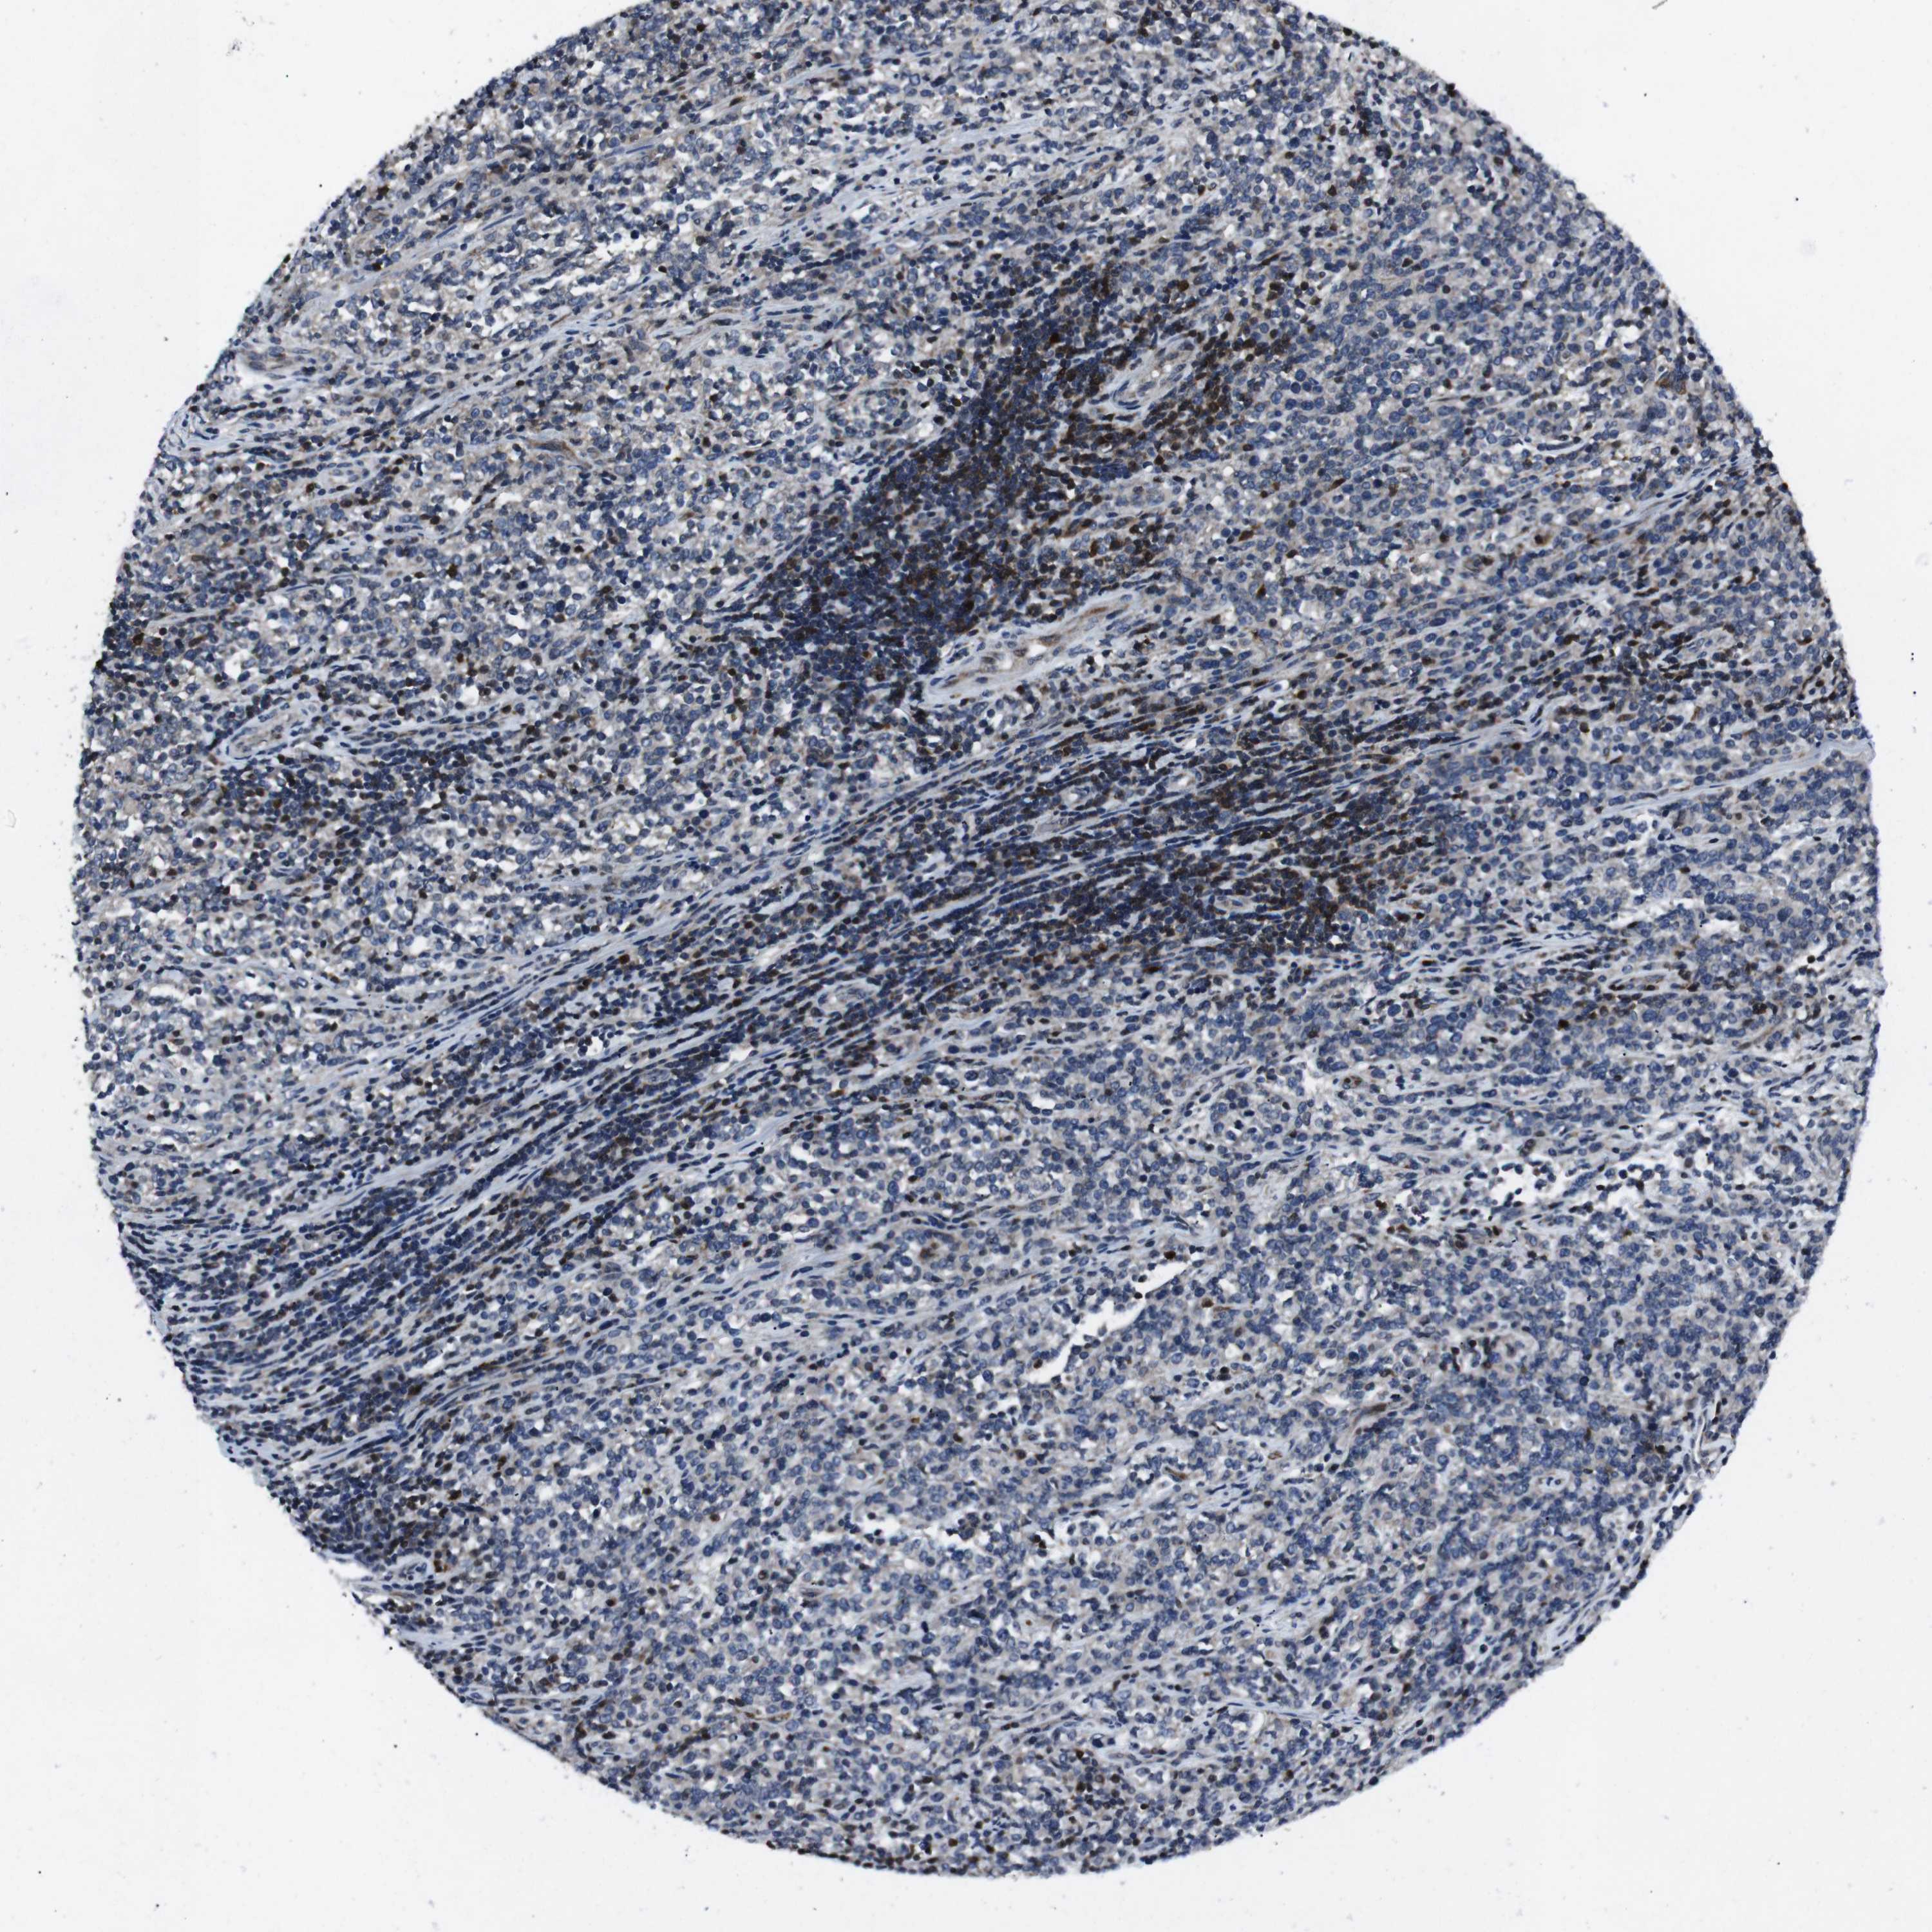

CANCER LYMPHOMA Show tissue menu

LYMPHOMA - Protein expressioni

A mouse-over function shows sample information and annotation data. Click on an image to view it in a full screen mode. Samples can be filtered based on level of antibody staining by selecting one or several of the following categories: high, medium, low and not detected. The assay and annotation is described here.

Each image is clickable and will lead to virtual microscopy that enables deeper exploration of all samples and also displays staining intensity scores, fraction scores and subcellular localization as well as patient and tissue information for each sample.

Antibody HPA001860

Antibody CAB013108

Staining

High

Medium

Low

Not detected

Intensity

Strong

Moderate

Weak

Negative

Quantity

>75%

75%-25%

<25%

None

Location

Nuclear

Cytoplasmic/membranous

Cytoplasmic/membranous,nuclear

Malignant lymphoma, non-Hodgkin's type, High grade

Hodgkin's disease, NOS

Malignant lymphoma, non-Hodgkin's type, Low grade